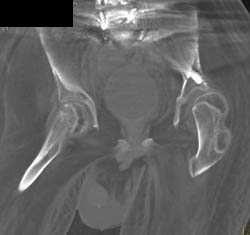

Normal Superficial Femoral Artery (SFA)